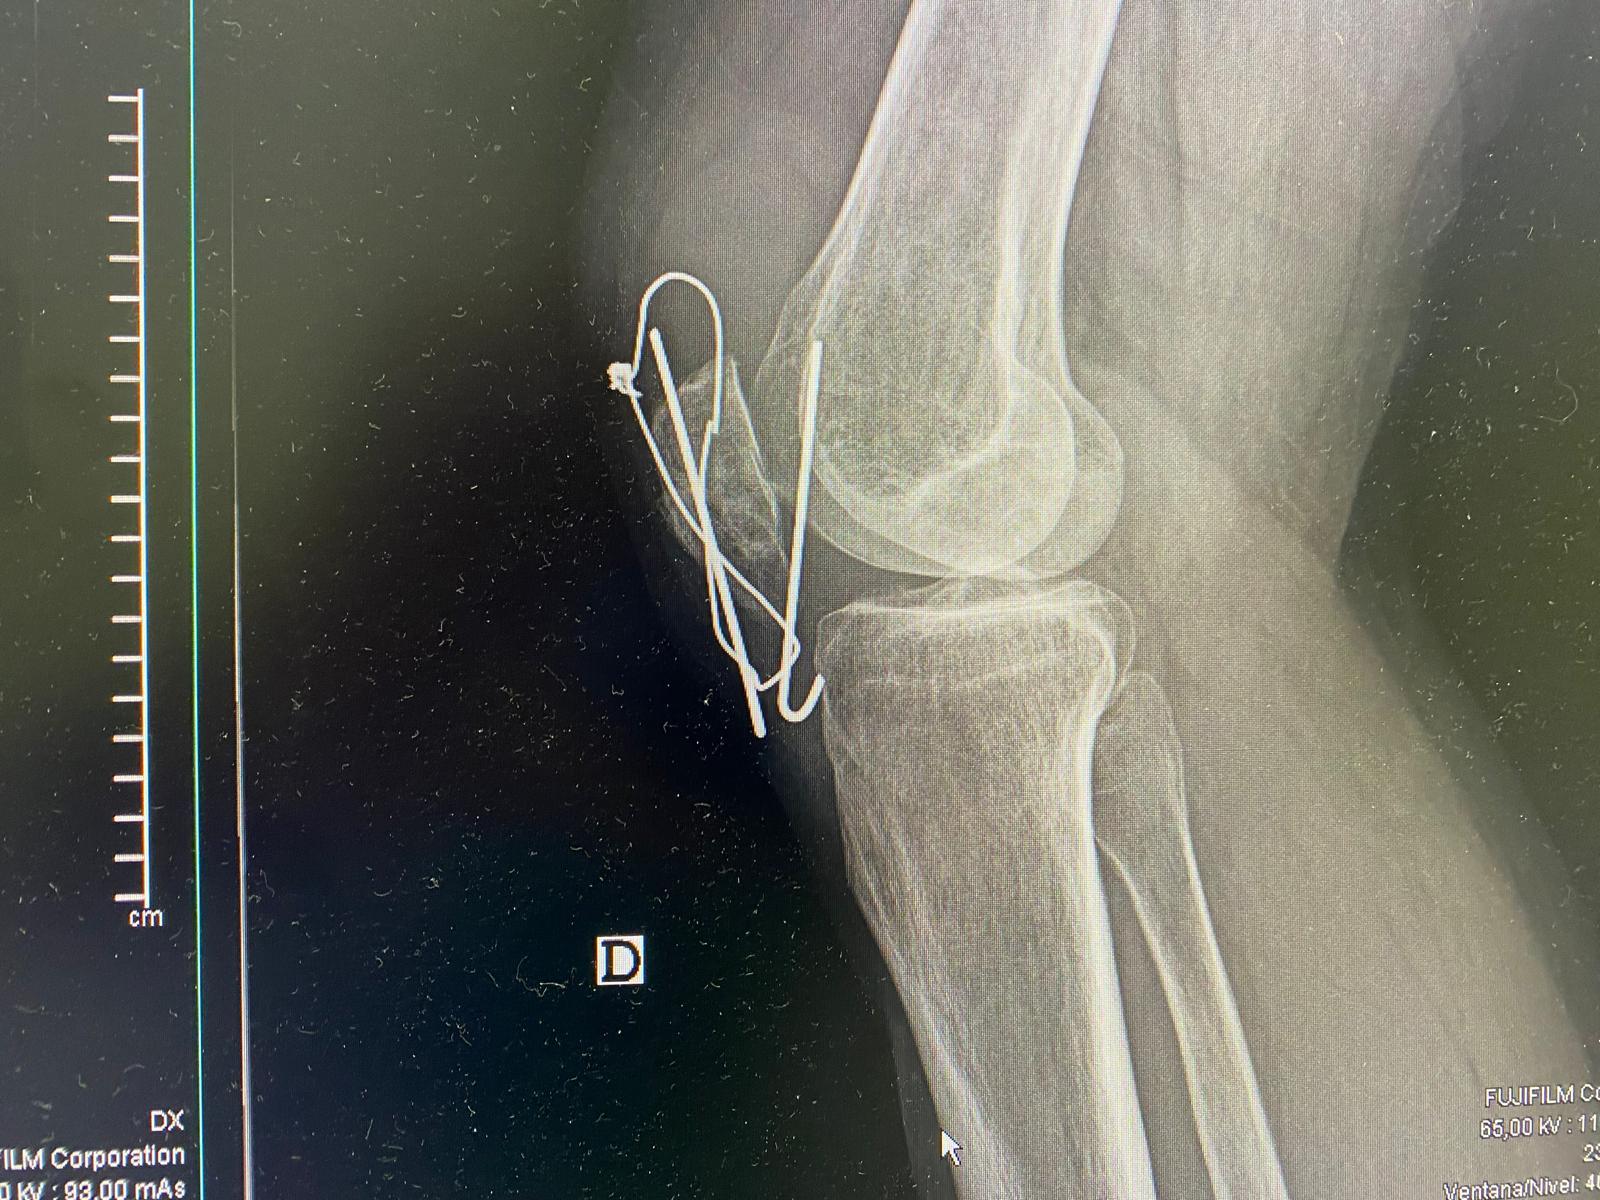

Dolor de rodilla derecha.

Juicio clínico, diagnóstico diferencial, identificación de problemas

Juicio clínico: Hemartros en contexto de rotura de material de osteosíntesis.